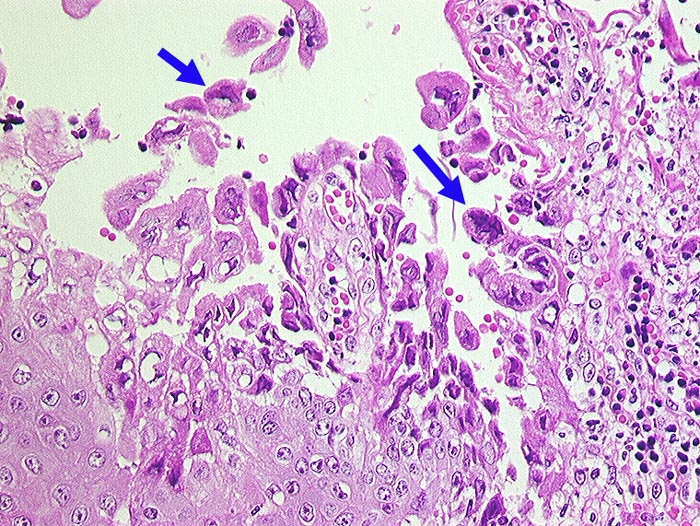

Ulzeröse Herpesglossitis

Ulzerierte Zungenschleimhaut. In der unmittelbaren Ulkusumgebungb teils mehrkernige Plattenepithelzellen mit Milchglaskernen.

T-Zell Lymphom mit leukämischer Ausschwemmung bekannt seit 3 Jahren. Infarktoide areaktive Pneumonie.